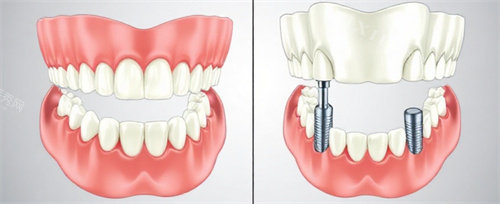

二、半口/全口种植牙价格:技术决定方案,方案影响费用

半口或全口缺牙患者需根据牙槽骨条件选择种植方式,费用因技术复杂度差异显著。

半口种植牙:4-6颗植体支撑

传统固定桥修复:需植入4-6颗植体,搭配烤瓷或全瓷桥,费用约2.5万-5万元;

All-on-4/6即刻种植:通过斜向植入技术减少植体数量,即刻负重,费用约4万-8万元(含植体、桥架及牙冠);

分段式种植:分两次植入植体,适合骨量不足患者,费用约3万-6万元。

全口种植牙:8-12颗植体支撑

传统全口固定修复:需植入8-12颗植体,费用约6万-12万元;

All-on-4全口即刻种植:上下颌各植入4颗植体,费用约8万-15万元(含植体、桥架及牙冠);

个性化种植方案:根据牙槽骨三维扫描数据定制植体位置,费用约10万-20万元。

品牌选择:半口/全口种植牙常用植体品牌包括韩国登腾、美国皓圣、瑞士ITI、瑞典诺贝尔等,高端品牌因骨结合稳定性更优,价格普遍高于中低端品牌。